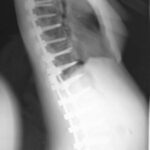

La diagnosi di una scoliosi è legata al sospetto clinico, come presenza di asimmetrie del corpo (spalle, fianchi, gibbo) ma, da definizione, per fare diagnosi di scoliosi deve essere presente una curva di 10°o superiore sul piano frontale, con rotazione vertebrale, misurati su una radiografia in piedi.

Si quando si ha il sospetto clinico di scoliosi. Ma non bisogna mai esagerare perché fanno male Le radiografie confermano la scoliosi, permettono di misurarla e quindi vedere quanto è grave e inoltre studiando il bacino è possibile vedere a che punto è lo sviluppo scheletrico.